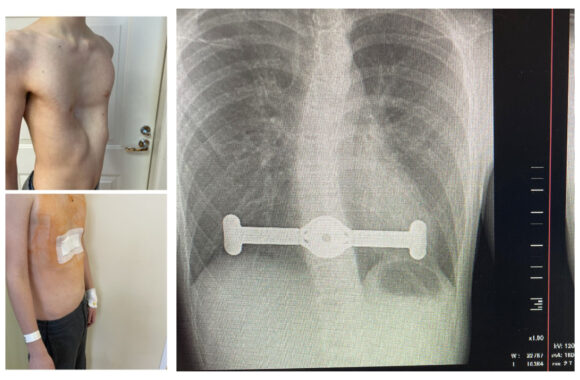

Įdubusiai krūtinės ląstai gydyti pirmąsyk panaudotas naujausias metodas